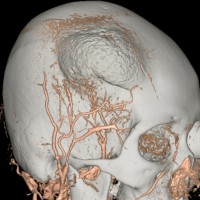

骨内髄膜腫 osseous meningioma

骨内増殖をする髄膜腫です。頭蓋骨腫瘍と間違えるようなものです。触った感じは骨腫ですが,CTでは,表面が毛羽立っていて,頭蓋冠に浸潤していることが特徴です。浅側頭動脈からの豊富な血流があります。

わずかですが頭蓋内にも腫瘍があり,硬膜が肥厚してガドリニウム増強されます。

頭蓋骨をかなり広範におかすので骨は捨てません。開頭して取り外した骨の厚くなっている部分と髄膜腫で軟らかくなっている部分を削除して,それから骨片をオートクレーブで短時間熱処理して,元あった所にもどします。下の画像は手術後1年半が経過したものですが,髄膜腫の再発はなく,熱処理骨弁は吸収されないで生着しています。